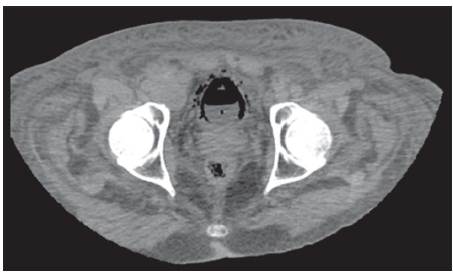

Se recibe reporte de patología, el cual evidencia tumor neuroendocrino tipo células de Merckel; entonces se valora por Oncología, donde indican inicio de quimioterapia ambulatoria, una vez se dé el egreso hospitalario. Una semana después el paciente presenta hematuria franca y oliguria; en estudios de laboratorios evidencian uroanálisis con hematuria, proteinuria en rango nefrótico y sedimento activo, con función renal dentro de parámetros de normalidad. Dados los nuevos hallazgos clínicos y el antecedente de diabetes, se decide solicitar estudios adicionales, descartando por oftalmología retinopatía diabética; adicionalmente el equipo de Nefrología descarta síndrome nefrótico, al evidenciar orina de 0,3 g en 24 horas, hipoalbuminemia y perfil lipídico normal; así mismo la morfología globular se encontraba en el 60% de hematíes eumorfos, descartando glomerulopatías. Investigando el origen de la hematuria, se complementa con estudios anatómicos; en efecto, se inicia con ecografía de vías urinarias que reportan buena diferenciación cortico-medular con riñones conservados de tamaño; posteriormente se solicita UROTAC para observar el tracto urinario bajo, evidenciándose engrosamiento de la pared vesical, gas perivesical como se observa en las imágenes 1, 2 y 3, y con conglomerados ganglionares retroperitoneales, hallazgos compatibles con cistitis enfisematosa.

Imagen 2 UROTAC en corte sagital en el que se evidencia contenido particulado dentro de vejiga y gas perivesical.

Dado el hallazgo anterior se solicita urocultivo y baciloscopia en orina para determinar la etiología, y adicionalmente se pide valoración por urología, descartando indicación de manejo quirúrgico. Las baciloscopias seriadas de orina son negativas y en el urocultivo se aisla E. coli patrón BLEE; se indicó continuar manejo antibiótico con ertapenem por 14 días y seguir con sonda vesical; posteriormente cesa hematuria macroscópica y aumento el gasto urinario. En relación con conglomerados ganglionares descritos, se planteó posible compromiso tumoral para posterior seguimiento de forma ambulatoria con servicio de oncología. Ver cuadro paraclínicos.